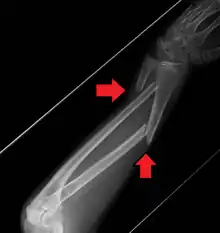

A fracture of the forearm can be classified as to whether it involves only the ulna (ulnar fracture), only the radius (radius fracture), or both radioulnar fracture.

For treatment of children with torus fractures of the forearm splinting appears to work better than casting.[7] Genetically determined disorders like hereditary multiple exostoses can lead to hand and forearm deformities. Hereditary multiple exostoses is due growth disturbance of the epiphyses of the radius and ulna, the two bones of the forearm.[8]